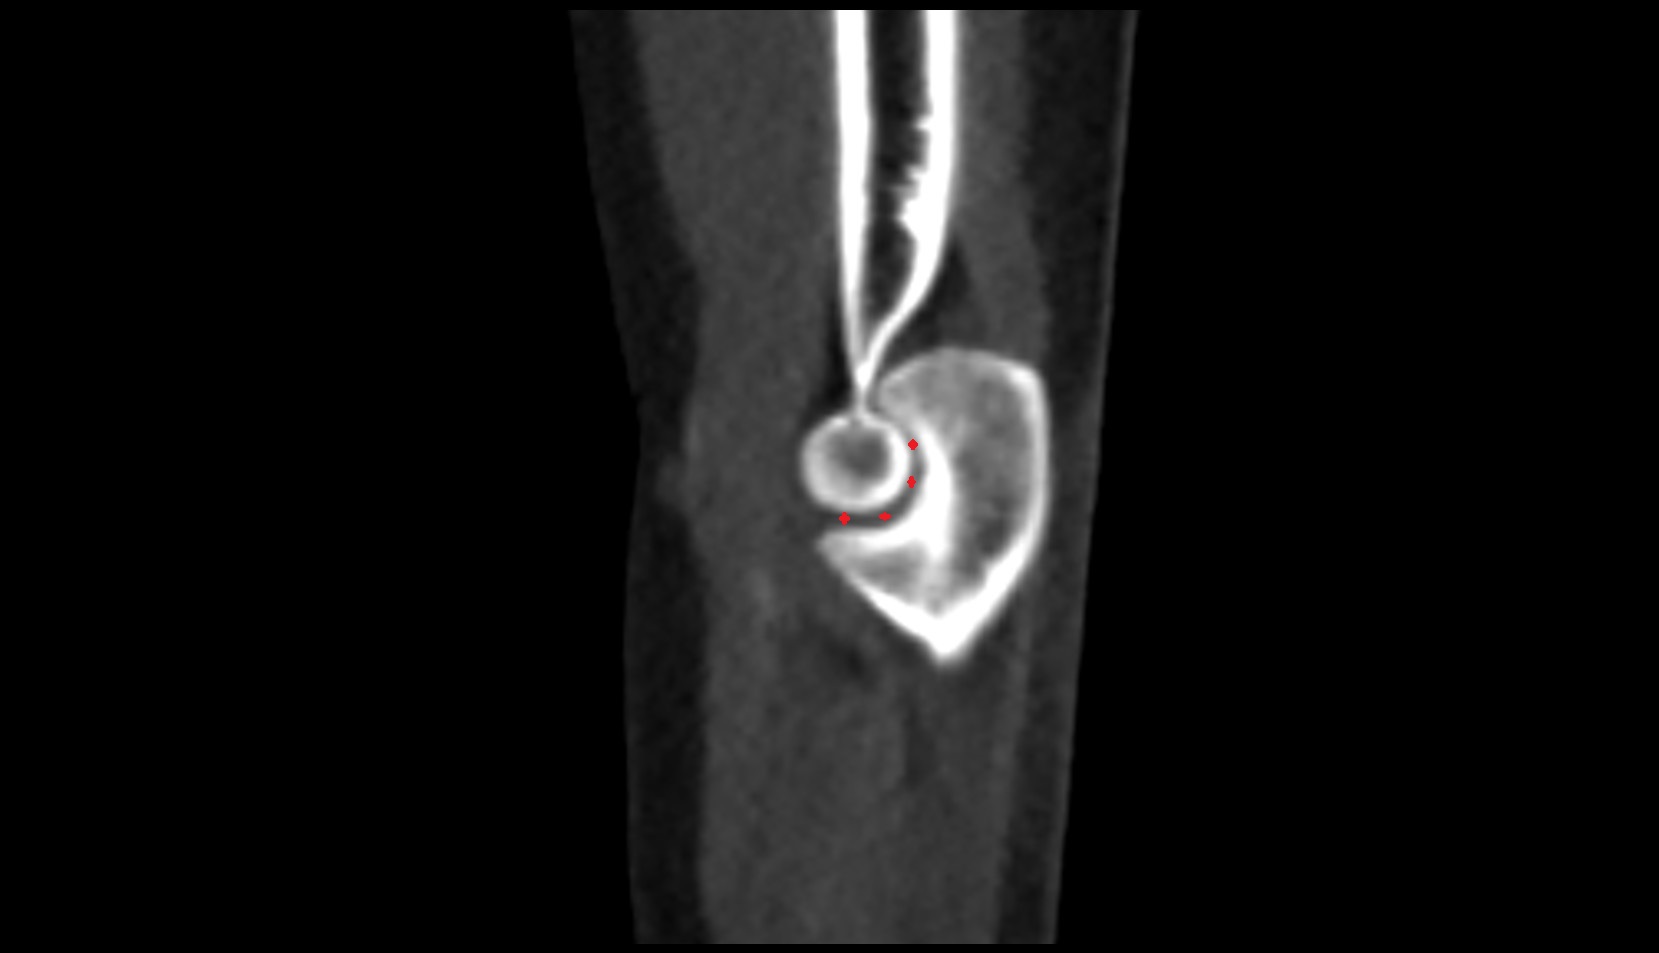

- Knee Joint